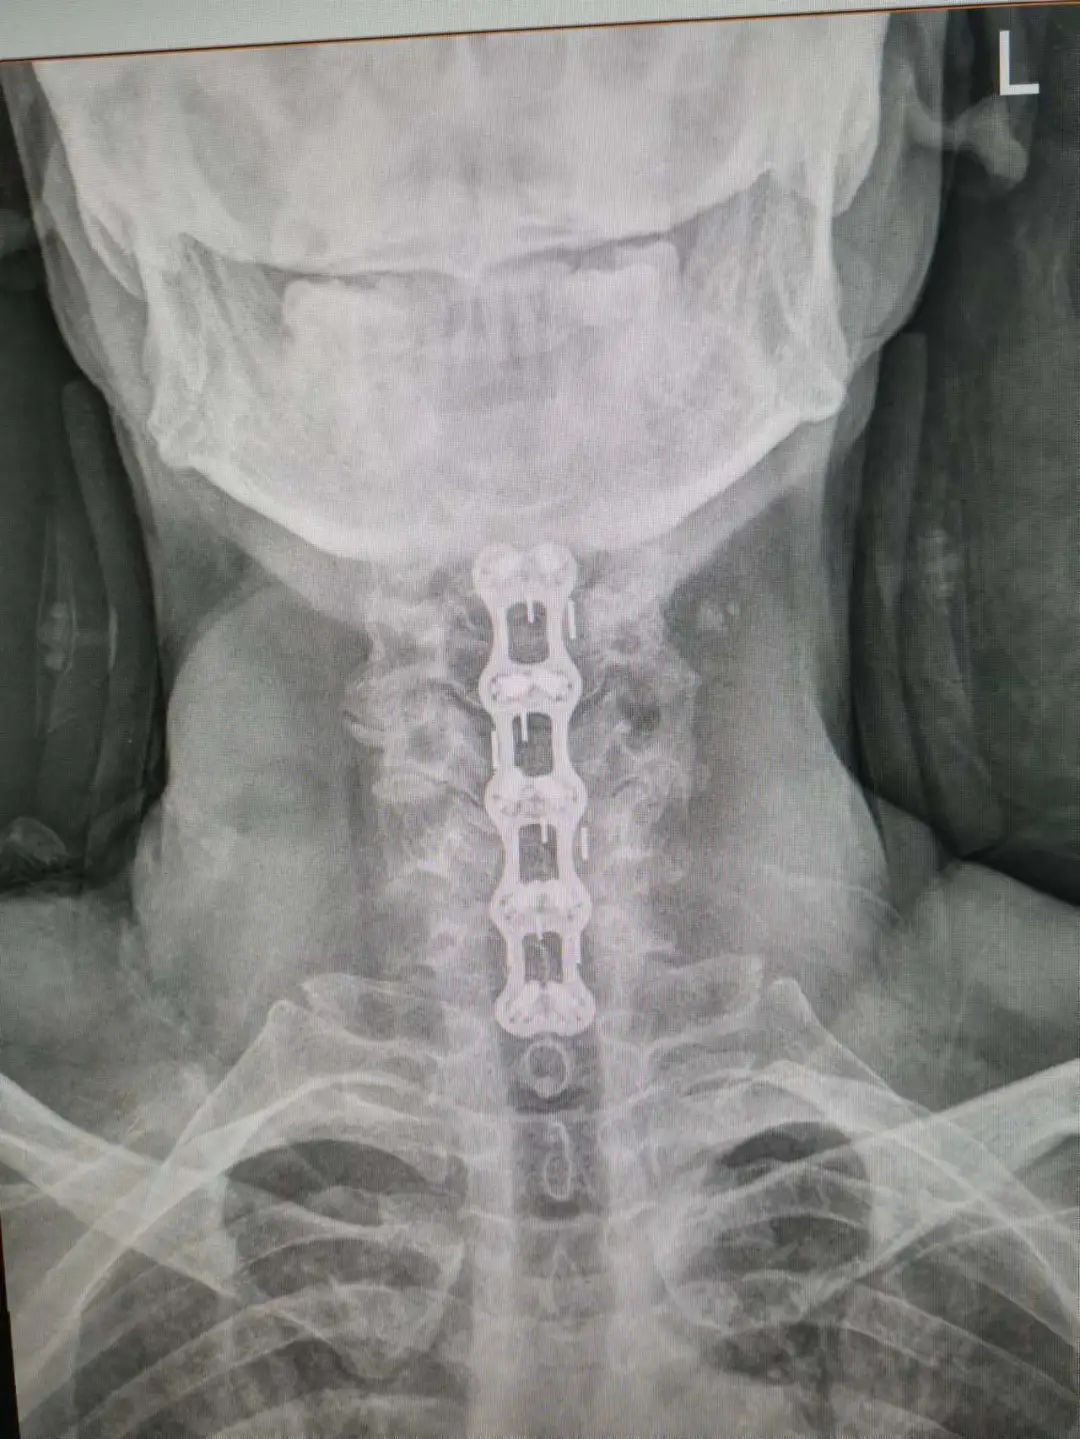

杨先生术后拍片

由于杨先生是高龄老人,很多脊柱外科医生都不敢触碰,对上颈椎手术更是望而生畏,但患者的病情刻不容缓,在科主任杨陈一与主治医生杨强的严谨细致地配合下,成功为杨先生做了手术。经过数日的康复治疗,杨先生的病情明显好转,现已出院。